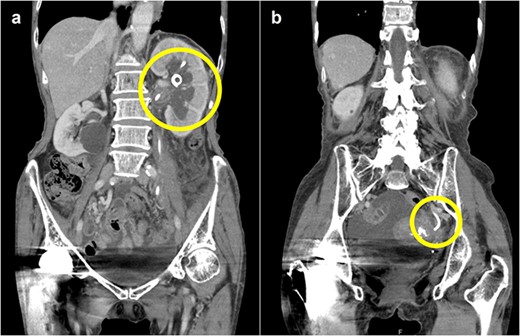

A 78-year-old woman (height, 161 cm; weight, 35 kg) had undergone total gastrectomy for gastric cancer; pathological examinations had revealed signet ring cell carcinoma with invasion into the serosa. One year and 4 months after the surgery, she presented to our hospital with fever, anorexia and weight gain. Computed tomography (CT) revealed left ureteral stricture and hydronephrosis caused by recurrent peritoneal dissemination (Fig. 1). Blood tests revealed decreased renal function and an increase in the inflammatory response. Based on these findings, a diagnosis of left obstructive acute pyelonephritis was made, prompting a decision to place a ureteral stent to relieve the obstruction. Using a flexible cystoscope fluoroscopically, a 6 Fr, 24 cm double-J ureteral stent was inserted into the left ureter. The guidewire passed smoothly, and good coiling was achieved both proximally and distally with no apparent complications (Fig. 2). Two weeks after stent placement, the patient recovered with improvements in left hydronephrosis and renal function.

Abdominal CT scan; (a) CT demonstrates the position of proximal coil formation in the left renal pelvis; (b) CT demonstrates proximal stent migration into the ureter.